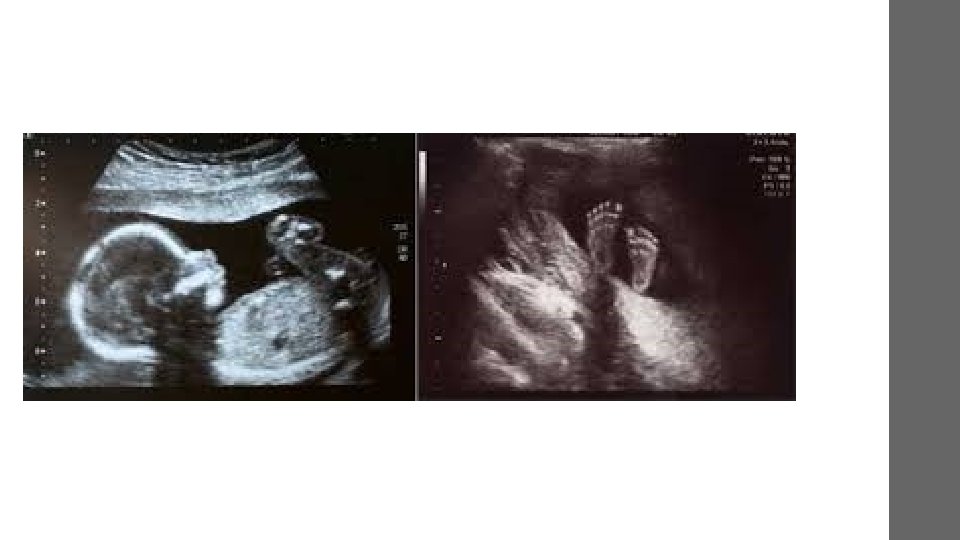

Applications in Obstetrics • Follow fetal development • Detect pathologies • Two-dimensional B-mode Ultrasound image and 3 D image of a fetus